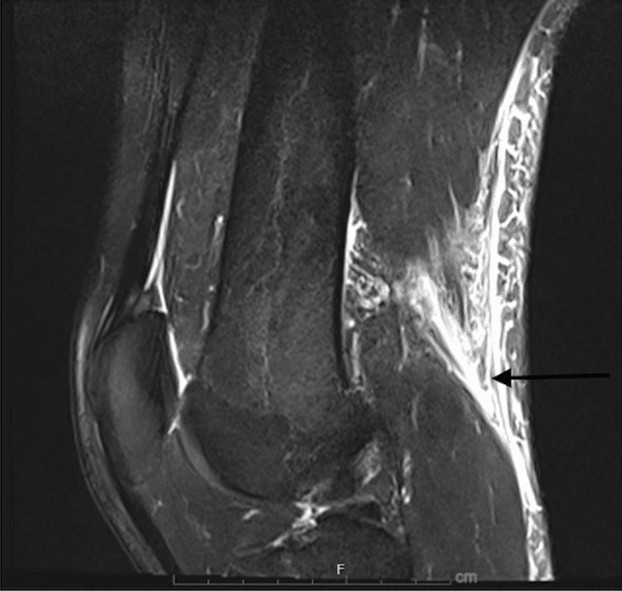

Given the clinical findings, an MRI of the left knee was obtained the same day, shown in Figures 1-3. Imaging revealed a near-complete tear of the distal biceps femoris tendon at the musculotendinous junction, approximately 5 cm proximal to its fibular insertion. Importantly, the tendon remained in continuity with the fibular head, with no frank avulsion. The lateral collateral ligament and posterolateral corner structures appeared intact [7].

Figure 1. MRI (sagittal view) of initial injury. The black arrow is pointing to musculotendinous disruption with some retraction of the distal biceps femoris tendon with overlying edema.